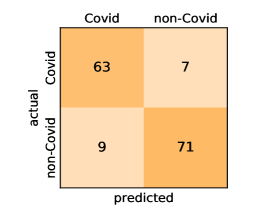

Here, we present and discuss the obtained results for detecting COVID-19 on the considered CT image datasets with different deep networks. We report the quantitative results along with the confusion matrices for every single architecture of the adopted networks.

On the SARS-CoV-2 CT dataset, ResNet101 achieves the best overall performance with respect to almost all evaluation metrics, with an average accuracy and F1-score of and , respectively. The model also achieves an average sensitivity rate of indicating that, on average, only two COVID-19 images are falsely predicted as negatives. It is also powerful enough to correctly identify all Non-COVID-19 cases with only one false positive resulting a specificity rate of . The highest sensitivity score of is achieved by the InceptionV3 model, where only one COVID-19 image is falsely predicted as negative on average. The SqueezeNet model obtains the lowest performance with respect to all evaluation metrics with a fairly acceptable average accuracy and sensitivity scores of and , respectively. Also the ShuffleNet architecture obtains satisfactory performance with approximately improvements on average for all metrics compared with SqueezeNet. Although the results obtained by these models are inferior compared with the rest of models, but they are more efficient. This matches their main objective of reducing the computational costs rather than improving their visual recognition abilities. The rest of models achieve competitive performance and very promising results with slight performance differences. Comparing the different variants of ResNet and DenseNet, we can see that the deeper variants from each architecture yield a slightly better performance. The deeper ResNet101 and ResNeXt101 show a marginal gain in performance compared with their shallower counterparts. The details about class-wise results for each model are summarized in the confusion matrices in Figure 9.

Our models achieve fairly good performance compared with the recently published work using the exact network architectures. This can bet attributed to a better optimization of our models and the effectiveness of our fine-tuning strategy using custom-sized inputs determined specifically for each architecture. Here, we see that DenseNet201 outperforms all other architectures. The model achieves average accuracy and sensitivity scores of and , respectively. It also identifies all COVID-19 images with only four images, on the average, are falsely predicted as Non-COVID-19. DenseNet169 achieves the second best average accuracy of and a very high sensitivity identical to the best model. The DenseNet121 and Xception models have nearly identical results for all evaluation metrics. We observe that small-sized networks such as ResNet18 achieves comparable results with other deeper models. The SqueezeNet and ShuffleNet models perform at a similar level of accuracy. The variants of the ResNeXt models have comparable results and perform as good as the different ResNet variants. A detailed analysis on the class-wise results for individual models is presented in the confusion matrices in Figure 10.